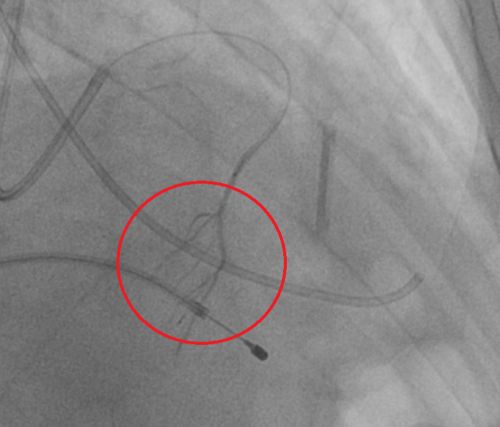

栓塞成功后远端血管闭塞。